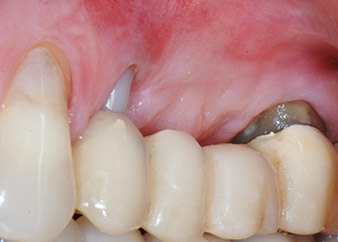

Fig. 1: Paziente di 58 anni. La radiografia preoperatoria mostra una lesione periodontale apicale in corrispondenza del dente 24 e una perdita orizzontale di tessuto osseo alveolare nel secondo quadrante.

Una paziente donna di 58 anni lamentava dolore e aumentata mobilità del dente di appoggio del ponte 24. Era presente infiammazione periodontale con tasche di profondità di 7 mm a livello mesiobuccale e di più di 12 mm a livello distale, nonché coinvolgimento di terzo grado della forcazione. Inoltre, la radiografia rivelava una lesione periodontale estensiva attorno alla regione apicale del dente pretrattato 24 (in altro luogo) a livello endodontico (Fig. 1).

Un anno più tardi, sono stati estratti i denti 25 e 26 in seguito a trauma e per motivi endoperiodontali, prima del posizionamento del ponte. Era stata diagnosticata una lesione endoperiodontale combinata in corrispondenza del dente 24, di eziologia incerta. La paziente desiderava conservare i denti 24 e 27 di appoggio al ponte e non accettava una protesi rimovibile finale, o temporanea. Si è pertanto deciso di fare il possibile per conservare entrambi i denti, nonostante la prognosi negativa basata sugli esiti clinici e radiologici.